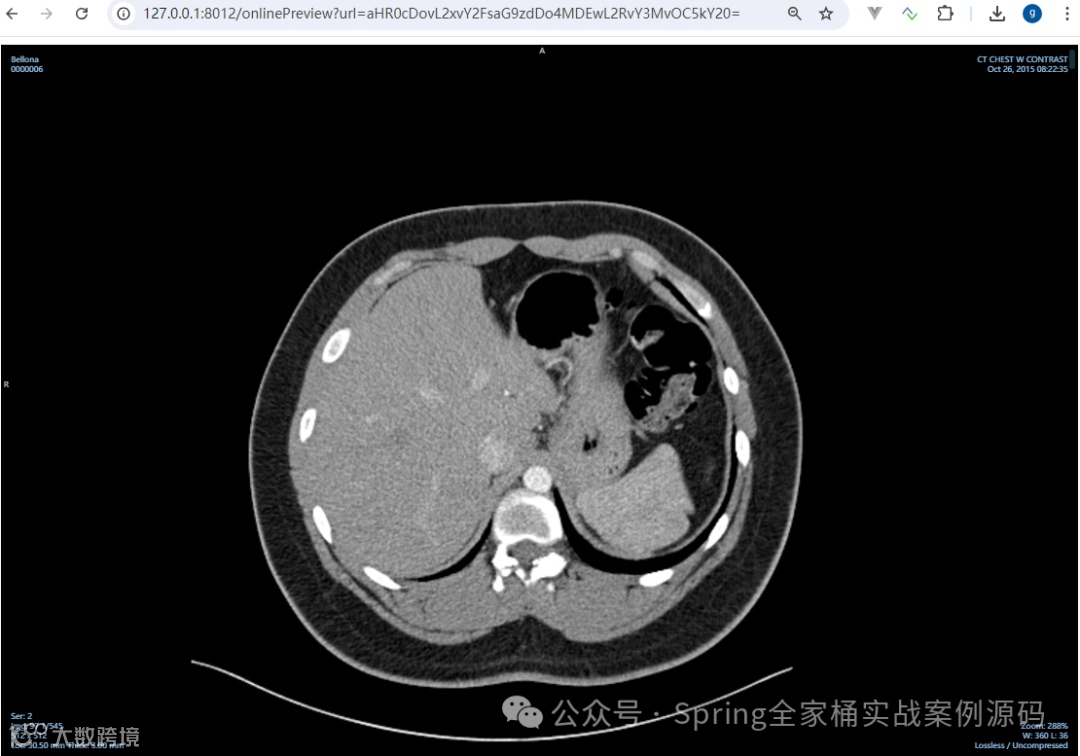

支持 dcm 等医疗数位影像预览

影响文件DCM